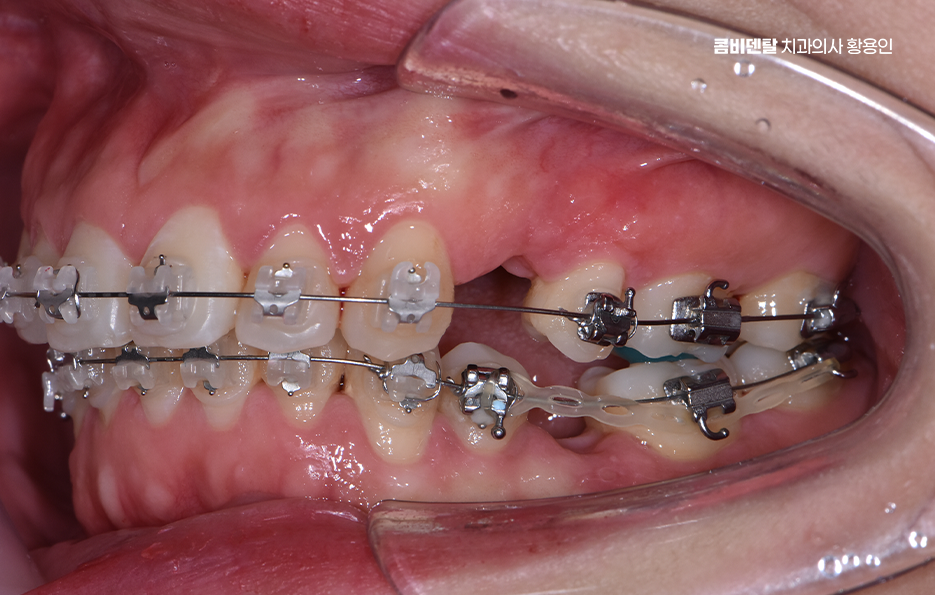

돌출입 팔자주름 교정 치아를 어떻게 움직이느냐에 따라 얼굴 인상이 달라지는 것인데 돌출입 교정은 일반적으로 소구치 네 개를 발치한 후, 앞니를 뒤쪽으로 밀어넣고 악궁을 재배열하는 방식으로 진행되며 앞니가 뒤로 이동하고 자연스럽게 입술이 들어가게 되고, 입술 돌출도가 줄어들면서 얼굴이 전반적으로 부드럽고 조화로운 느낌으로 바뀔 수 있어요

옆모습에서 입이 덜 나와 보이고, 턱선이 또렷해지는 것도 이런 원리에서 비롯되며 치아 배열 자체는 물론이고, 입술과 턱 근육의 균형이 맞춰지기 때문에 얼굴 인상이 부드럽고 안정적으로 바뀌는 거예요.

돌출입 팔자주름 교정 그럼 팔자주름은 어떻게 변하느냐는 질문도 많은데 돌출입이 있는 사람들은 입 주변 근육에 지속적으로 긴장이 들어가기 때문에 팔자주름이 더 도드라져 보이는 경우가 많고 입술이 앞으로 나와 있다 보니, 코 밑에서부터 입꼬리로 이어지는 주름이 더 깊게 파이고, 표정이 굳어 보일 수도 있었어요.

그런데 치아를 뒤로 이동시키면서 입술이 안쪽으로 정리되면, 입 주변의 긴장도 줄어들게 되고, 자연스럽게 팔자주름이 완화되는 효과가 생기는 것이며 물론 주름 자체를 없애는 시술처럼 극적인 효과는 아니지만, 돌출이 줄어들면서 팔자주름이 덜 도드라져 보이고 얼굴의 입체감이 개선되는 건 분명한 변화라고 볼 수 있어요